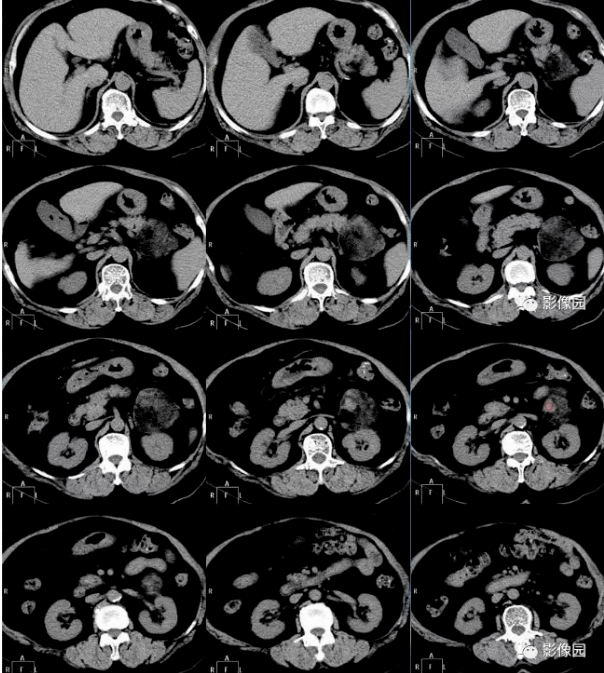

肾脏典型病例分享之血管平滑肌脂肪瘤影像学表现

图片尺寸1599x999